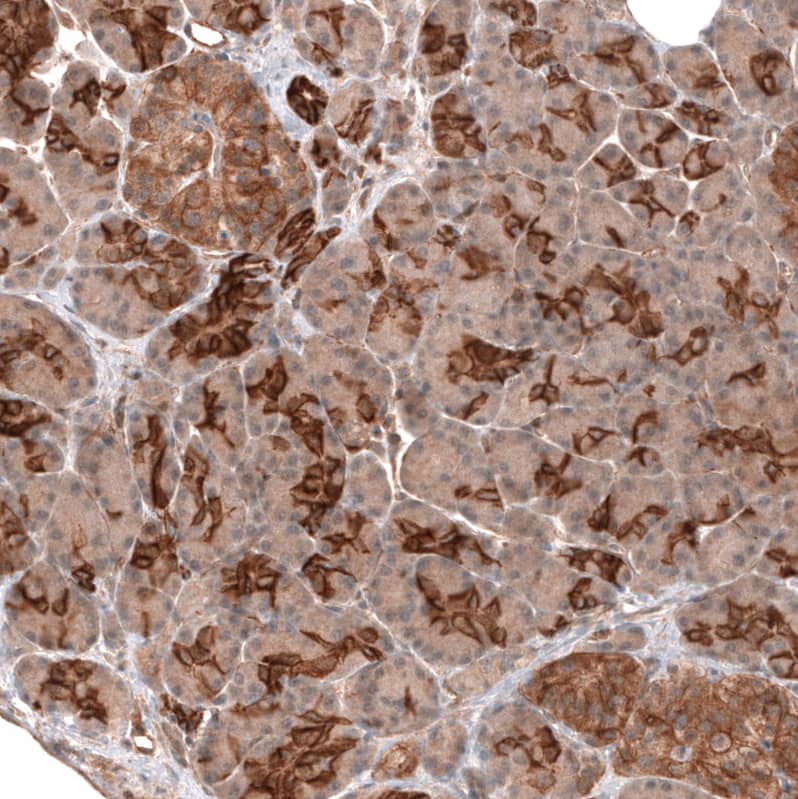

FXYD5/Dysadherin Antibody (CL14037) - Azide and BSA Free Immunohistochemistry-Paraffin: FXYD5/Dysadherin Antibody [NBP3-43835]

Immunohistochemistry-Paraffin: FXYD5/Dysadherin Antibody [NBP3-43835]

Staining of human pancreas shows strong membranous positivity in exocrine glandular cells.